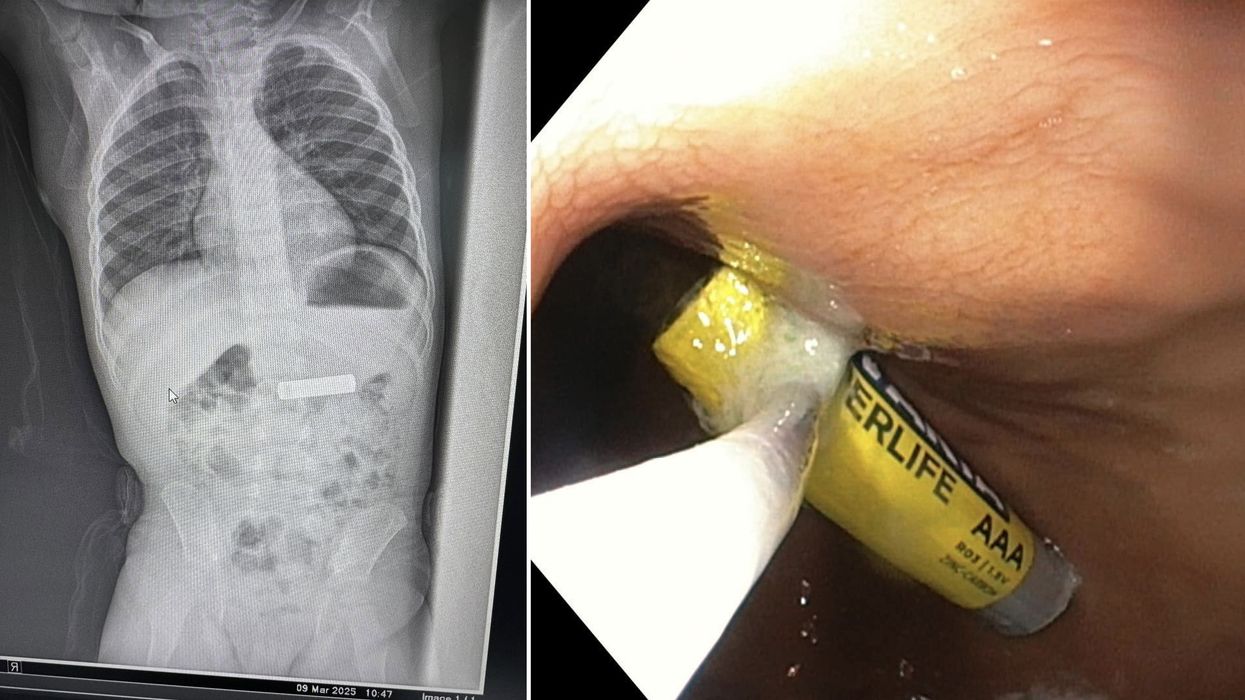

Gastroenterologu në Gjilan ia largon dyvjeçarit baterinë e telekomandës nga stomaku

Gastroenterologu Besnik Elezi ka realizuar me sukses heqjen e një baterie telekomande nga stomaku i një fëmije 2-vjeçar.

“Largohet nga stomaku bateri e telekomandës te fëmija 2 vjeç K.Sh.”, ka shkruar Elezi, duke ndarë edhe disa fotografi nga procedura.

Më poshtë mund të shihni imazhet e publikuara nga vetë mjeku.